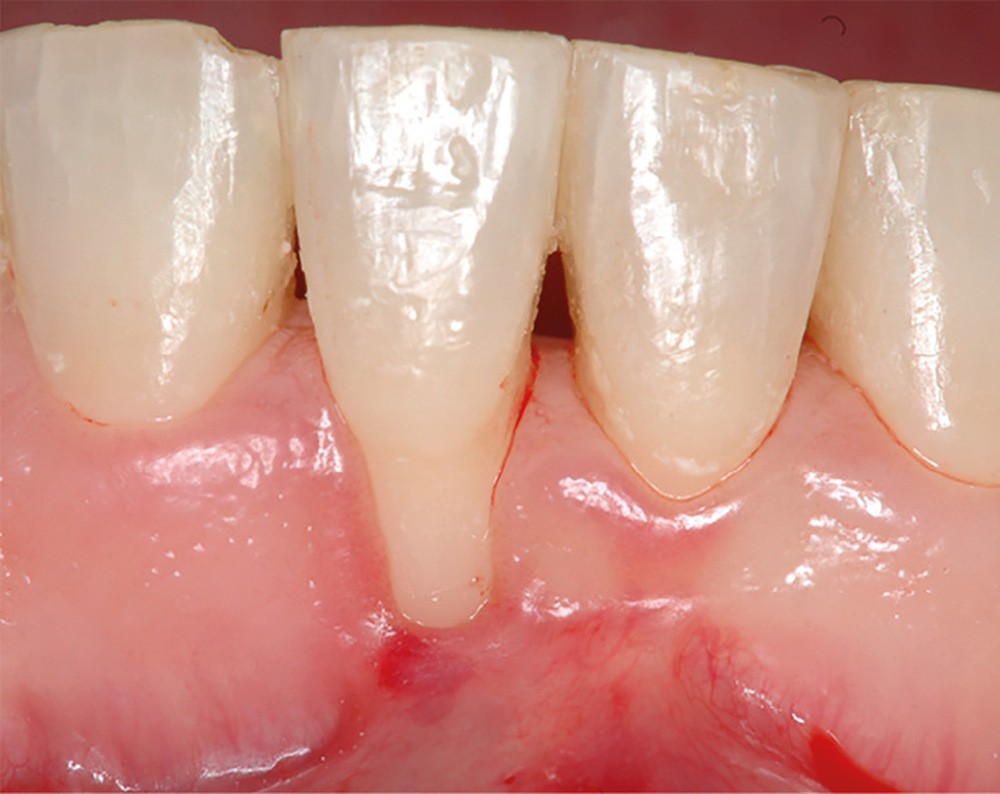

En plus du contexte parodontal, le type de mouvements orthodontiques envisagés est à considérer. Dans le secteur incisivo-canin mandibulaire, un des objectifs classiques du traitement orthodontique est le repositionnement de l’incisive dans un axe compatible avec des relations inter-arcades harmonieuses (≤ 95°). Dans certains cas, l’objectif à atteindre peut se traduire par un mouvement de la racine vers le vestibule. Ce mouvement est considéré comme à risque et peut aggraver une situation parodontale initiale non favorable. Face à une situation clinique complexe, il est possible de synthétiser les facteurs positifs et négatifs et considérer que l’accumulation de deux facteurs négatifs conduit à la recommandation d’adresser le patient chez un parodontiste (tableau 1).